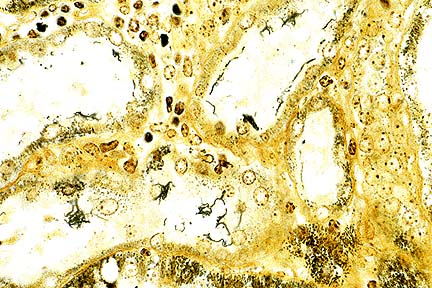

Numerous, delicate, 5 to 20 m long spirochetes consistent with Leptospira sp. within proximal renal tubules in a 6-month-old pigs. (Warthin-Starry 4.0, 400X, 56K)

Conference Note: The Warthin-Starry method demonstrated numerous, delicate, 5 to 20 m long spirochetes consistent with Leptospira sp. within the proximal renal tubules. The single diagnosis of tubulointerstitial nephritis was chosen because the participants were not certain that two separate pathologic processes were involved.